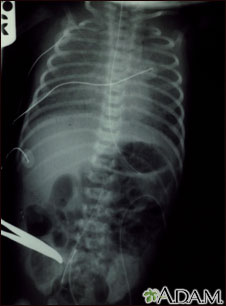

Totally anomalous pulmonary venous return, x-ray

Totally anomalous pulmonary venous return (TAPVR) is a form of congenital heart disease.